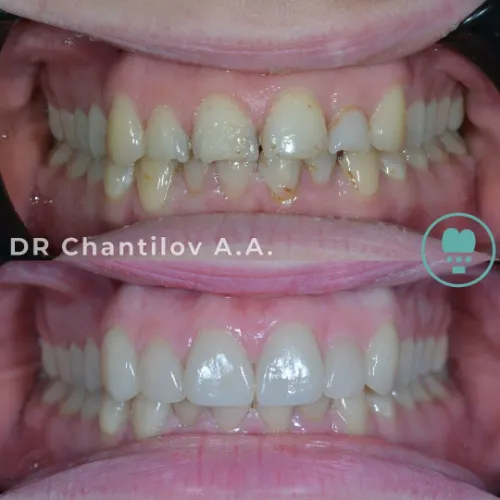

лечение и эстетика

реставрация зубов